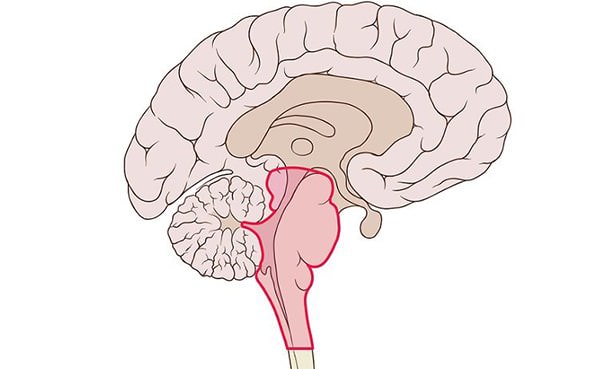

Ствол головного мозга – наиболее древний отдел центральной нервной системы, соединяющий его со спинным мозгом. Он контролирует дыхание, частоту сердечных сокращений, уровень артериального давления, сон, сексуальное возбуждение, бодрствование, процесс глотания, движение глаз. Через ствол проходят нервные пути, передающие сигналы от мозжечка мышцам.

Стволовой инсульт – это острое нарушение мозгового кровообращения, при котором поврежденный мозг теряет контроль над самыми жизненно важными органами – сердцем, легкими.